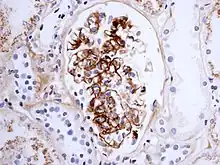

Morphology

Histologically, IgA nephropathy may show mesangial widening and focal and segmental inflammation. Diffuse mesangial proliferation or crescentic glomerulonephritis may also be present. Immunofluorescence shows mesangial deposition of IgA often with C3 and properdin and smaller amounts of other immunoglobulins (IgG or IgM). Early components of the classical complement pathway (C1q or C4) are usually not seen. Electron microscopy confirms electron-dense deposits in the mesangium that may extend to the subendothelial area of adjacent capillary walls in a small subset of cases, usually those with focal proliferation.

The disease derives its name from deposits of immunoglobulin A (IgA) in a granular pattern in the mesangium (by immunofluorescence), a region of the renal glomerulus. The mesangium by light microscopy may be hypercellular and show increased deposition of extracellular matrix proteins. In terms of the renal manifestation of Henoch–Schönlein purpura, it has been found that although it shares the same histological spectrum as IgA nephropathy, a greater frequency of severe lesions such as glomerular necrosis and crescents were observed. Correspondingly, HSP nephritis has a higher frequency of glomerular staining for fibrin compared with IgAN, but with an otherwise similar immunofluorescence profile.[4]

For an adult patient with isolated hematuria, tests such as ultrasound of the kidney and cystoscopy are usually done first to pinpoint the source of the bleeding. These tests would rule out kidney stones and bladder cancer, two other common urological causes of hematuria. In children and younger adults, the history and association with respiratory infection can raise the suspicion of IgA nephropathy. A kidney biopsy is necessary to confirm the diagnosis. The biopsy specimen shows proliferation of the mesangium, with IgA deposits on immunofluorescence and electron microscopy. However, patients with isolated microscopic hematuria (i.e. without associated proteinuria and with normal kidney function) are not usually biopsied since this is associated with an excellent prognosis. A urinalysis will show red blood cells, usually as red cell urinary casts. Proteinuria, usually less than 2 grams per day, also may be present. Other renal causes of isolated hematuria include thin basement membrane disease and Alport syndrome, the latter being a hereditary disease associated with hearing impairment and eye problems.